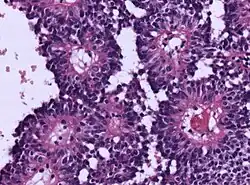

| Micrograph of an astroblastoma showing the characteristic nuclear pervivascular pseudorosette. H&E stain. | |

Astroblastoma is a rare glial tumor derived from the astroblast, a type of cell that closely resembles spongioblastoma and astrocytes.[1] Astroblastoma cells are most likely found in the supratentorial region of the brain that houses the cerebrum, an area responsible for all voluntary movements in the body.[2] It also occurs significantly in the frontal lobe, parietal lobe, and temporal lobe, areas where movement, language creation, memory perception, and environmental surroundings are expressed. These tumors can be present in major brain areas not associated with the main cerebral hemispheres, including the cerebellum, optic nerve, cauda equina, hypothalamus, and brain stem.[3]

Astroblastoma can be divided into low-grade, well-differentiated tumors and high-grade, anaplastic subtypes.[1] The majority of tumors exhibit a spherical perimeter with either a solid or cystic interior, comprising peripheral vasculature and epithelioid neoplasms.

Since the early 1890s, astroblastoma has established a stable set of pathological qualities that truly distinguishes itself as a separate and significant entity. Compilations from various case reports reveal the following common characteristics:[2]

- Radial arrangement as a pseudorosette

- Lacks "true rosette" architecture